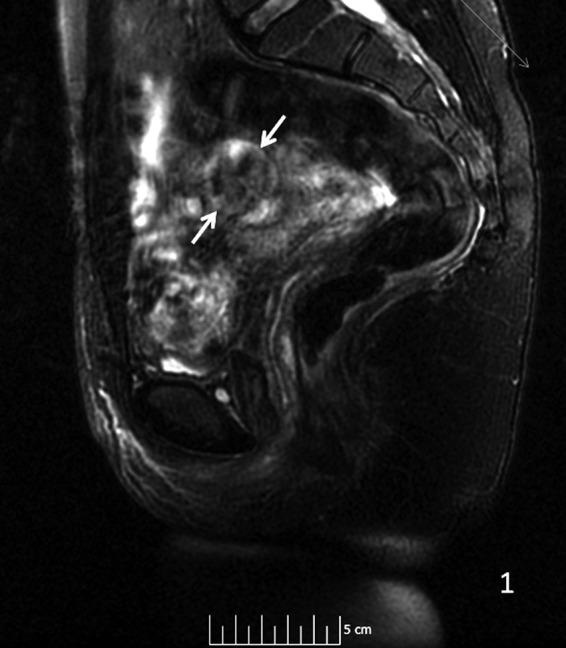

Adenomatoid uterine tumors are rare, and their appearance on medical imaging modalities is not well established. We present a case of an adenomatoid uterine tumor reviewing a unique sonographic presentation, magnetic resonance imaging (MRI), gross surgical appearance of the tumor, and microscopic pathology images. A 29-year-old gravida 0 Caucasian woman presented with dysmenorrhea, menorrhagia, and desire to conceive. Transvaginal ultrasound revealed a 2.7 cm round, well-circumscribed posterior intramural uterine mass. The mass was hyperechoic centrally with a thin hypoechoic rim. Color Doppler imaging revealed a prominent vascular rim around the periphery of the mass as well as central vascularity not typical for a leiomyoma. MRI, with and without intravenous gadolinium, was obtained showing a 2.7 cm posterior fundal mildly enhancing uterine mass suggestive of leiomyoma. The mass had a heterogeneous signal pattern on T2-weighted images, and no fat component was noted within the mass. Repeat transvaginal ultrasound showed interval growth of the mass to 3.5 cm with a lipomatous appearance. Adenomatoid uterine tumors are rare and may be mistaken for uterine leiomyomata. Unique features include sonographic appearance of central hyperechogenicity with a hypoechoic rim and prominent peripheral and central vascularity in conjunction with MRI revealing a heterogeneous signal pattern on T2-weighted images without fat component. Gross surgical appearance reveals a nondiscrete capsule and secretion of mucoid material when the mass is exposed. We present a case of adenomatoid tumor providing sonographic, MRI, surgical, and pathological correlation. The patient subsequently conceived spontaneously and delivered at term by cesarean section. The patient underwent a preoperative evaluation with complete blood count, comprehensive metabolic panel, blood type with antibody screen, and pregnancy test. She underwent laparoscopic excision with robotic assistance for removal of the tumor. Grossly, the uterine mass had a very soft consistency atypical for a uterine leiomyoma making dissection more challenging. During dissection the mass diffusely secreted a mucoid material although the capsule was not disrupted. The lesion was excised intact and was removed from the peritoneal cavity in an endocatch bag without internal morcellation. Microscopic examination revealed an adenomatoid tumor.

腺肌瘤样子宫肿瘤较为罕见,其在医学影像检查中的表现尚未完全明确。我们报告一例腺肌瘤样子宫肿瘤,回顾其独特的超声表现、磁共振成像(MRI)、肿瘤的大体手术外观及微观病理图像。一名29岁未孕的白人女性,因痛经、月经过多及有生育意愿前来就诊。经阴道超声检查发现一个2.7厘米圆形、边界清晰的子宫肌壁间后壁肿物。肿物中央呈高回声,周边有一薄层低回声边缘。彩色多普勒成像显示肿物周边有明显的血管环,且中央有血管分布,这并非平滑肌瘤的典型表现。行MRI检查,静脉注射钆对比剂前后成像显示一个2.7厘米的子宫底部后壁轻度强化肿物,提示为平滑肌瘤。该肿物在T2加权图像上信号不均匀,且肿物内未发现脂肪成分。再次经阴道超声检查显示肿物增大至3.5厘米,呈脂肪瘤样外观。腺肌瘤样子宫肿瘤较为罕见,可能被误诊为子宫平滑肌瘤。其独特特征包括超声表现为中央高回声、周边低回声边缘及明显的周边和中央血管分布,同时MRI显示T2加权图像上信号不均匀且无脂肪成分。大体手术外观显示肿物无明显包膜,肿物暴露时可见黏液样物质分泌。我们报告一例腺肌瘤样肿瘤,提供超声、MRI、手术及病理的相关性。患者随后自然受孕并足月剖宫产分娩。患者术前进行了全血细胞计数、综合代谢指标检测、血型及抗体筛查和妊娠试验等评估。她在机器人辅助下行腹腔镜肿瘤切除术。大体上,子宫肿物质地非常软,这与子宫平滑肌瘤不同,增加了手术分离的难度。手术分离过程中,肿物弥漫性分泌黏液样物质,尽管包膜未破裂。病变完整切除,装入内套袋从腹腔取出,未进行内部碎解。显微镜检查显示为腺肌瘤样肿瘤。